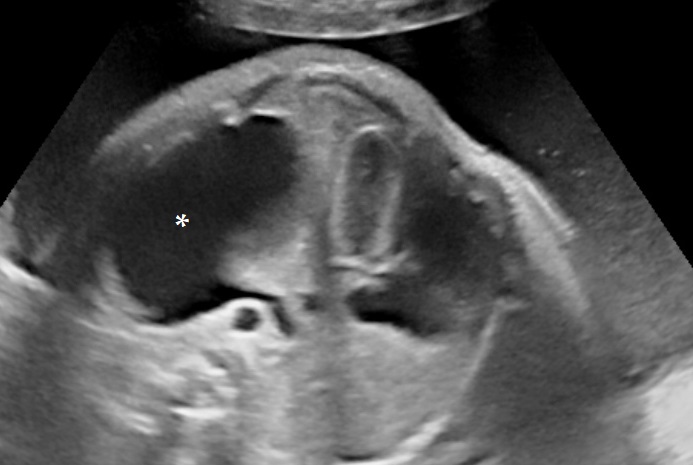

- Decreased swallowing

- gastrointestinal/tracheal obstruction (atresia, fistula, diaphragmatic hernia, micrognathia),

- Anatomy of the fetus and its movements should be examined carefully